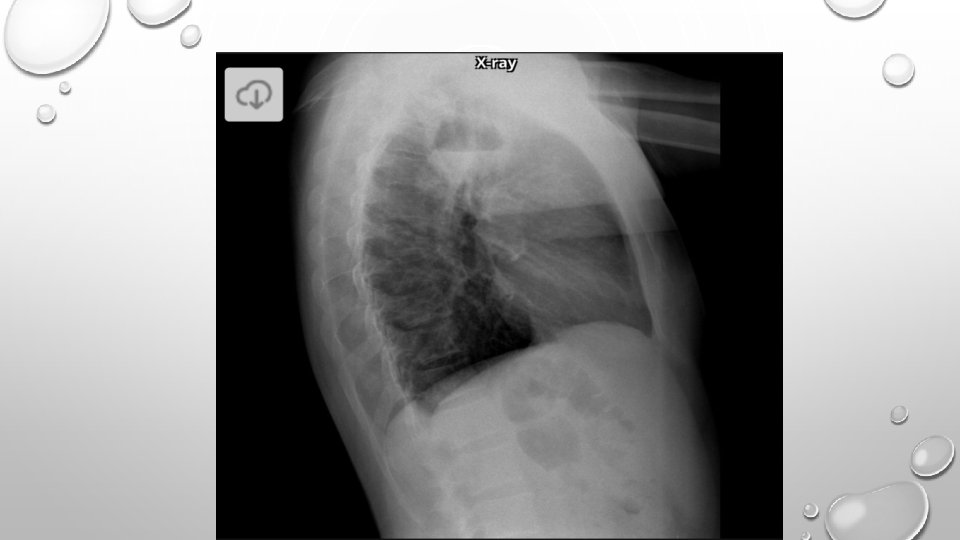

• LUNG ABSCESS REPRESENTS NECROSIS AND CAVITATION OF THE LUNG FOLLOWING MICROBIAL INFECTION • LUNG ABSCESS CAN BE SINGLE OR MULTIPLE

• LOCALIZATION OF INFECTION IN PRIMARY LUNG AB. IS IN POSTERIOR UPPER LOBE AND SUPERIOR LOWER LOBES • RIGHT LUNG IS AFFECTED MORE COMMONLY • MICROBIOLOGY IS POLYMICROBIAL • A PUTRID LUNG AB. REFERS TO CASES WITH FOUL SMELLING BREATH , SPUTUM, OR EMPYEMA

DIAGNOSIS • IMAGING • NEEDLE ASPIRATION